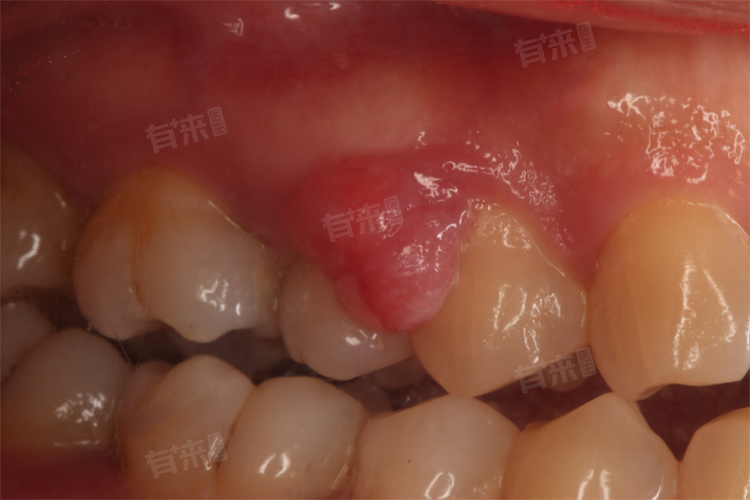

牙齿边上长了个肉包,这种情况在医学上可能由多种原因引起,如牙周炎、根尖周炎、智齿冠周炎等,还应选择合适的处理方式,例如保持口腔卫生等,旨在帮助患者有效应对并缓解症状。

- 引发疼痛与不适:肉包可能会刺激牙龈或周围组织,引发疼痛、肿胀和不适感。这种疼痛可能影响患者的日常生活和饮食。

- 增加感染风险:肉包组织容易滋生细菌,增加口腔感染的风险。如果不及时治疗,可能引发牙龈疾病、牙周炎等口腔问题,严重时甚至可能影响全身健康。